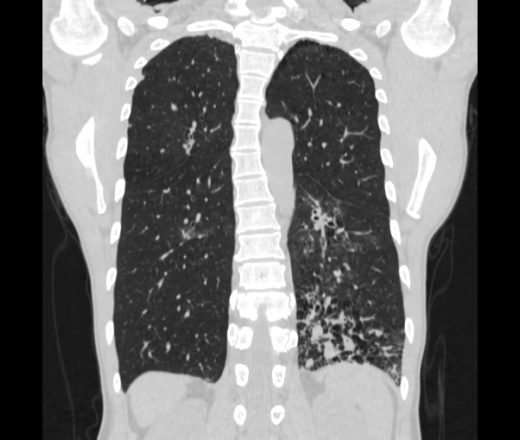

Мужчина пенсионного возраста. Цель назначения КТ ислючение зла в левом легком. Вижу тракционные бронхоэктазы с рубцовой эмфиземой по периферии, скорее всего БЭБ в стадии обострения. Дивертикулы трахеи. Выложил из за того что есть доля сомнения в отношении исключения зно3, немного смущают линии похожие на Керли.

Единственно, не сказал бы, что это тракционные бронхоэктазы, ну, и про линии Керли не вполне понял.

Ну да. Выразился не правильно. На фоне легочного рисунка усиленного линии похожие на септальные, не знаю как называются, при интерстиц.отеке похожие

На мой взгляд, это не главное, указал бы в описании - локально утолщен междольковый интерстиций, и всё